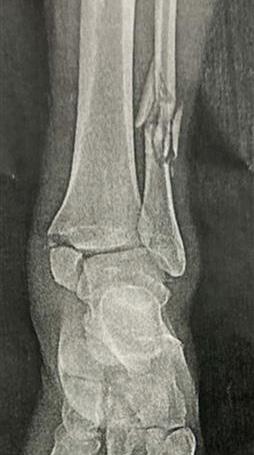

spécifiquement entraîné le modèle ChatGPT sur des images médicales. Cependant, il peut toujours faire quelques observations de base fondées sur ce qu’il sait de l’anatomie humaine. On a demandé à ChatGPT d’examiner la radiographie de face de l’extrémité inférieure du tibia et la cheville, et les résultats étaient surprenants (voir l’encadré à la page suivante). En effet, la capacité de ChatGPT à analyser et interpréter des images médicales à l’aide d’algorithmes de NLP constitue un avantage majeur en radiologie. Traditionnellement, les radiologistes analysent les images et interprètent leurs résultats de façon « manuelle », ce qui peut prendre du temps et engendrer des erreurs. Cependant, pour tirer parti de la précision du ChatGPT, ce dernier nécessite des particularités spécifiques adaptées aux images médicales analysées. En fournissant des détails et informations pertinentes sur les images, tels que les antécédents médicaux du patient, les symptômes et les caractéristiques de l’image, ChatGPT peut traiter et interpréter efficacement les images en temps réel, ce qui permet d’établir des diagnostics rapides et précis. Cette approche innovante réduit non seulement la charge de travail des radiologistes, mais améliore également l’efficacité et la fiabilité globales du processus de diagnostic. Les algorithmes du ChatGPT sont conçus pour reconnaître des indicateurs dans les images radiologiques et les interpréter d’une manière similaire à celle que feraient les radiologistes. Ils ont la capacité d’analyser une grande quantité de données à partir d’images médicales pour identifier ces indicateurs et anomalies et peuvent même apprendre des

Une radiographie de l’extrémité inférieure de la jambe gauche présentée au ChatGPT pour élaborer un rapport radiologique.

Voici les constatations de Dr ChatGPT :

■ Localisation de la fracture potentielle : La fracture potentielle semble située au milieu de la diaphyse du péroné. Les fractures des péronés médianes de la diaphyse peuvent être isolées ou accompagnées d’autres blessures, notamment au niveau de la cheville ou du tibia opposé.

Nature de la fracture

■ Déplacement : À première vue, la fracture ne semble pas déplacée, ce qui signifie que les fragments osseux sont étroitement alignés.

■ Complétude : La fracture semble complète et s’étend sur toute la largeur du péroné.

■ Orientation : La ligne de fracture semble quelque peu oblique lorsqu’elle traverse le péroné.

Résultats associés

■ Rupture corticale : Il semble y avoir une rupture nette dans le cortex du péroné, ce qui indique une fracture.

■ Tissus mous : Il est difficile de formuler des commentaires définitifs sur les lésions des tissus mous uniquement à partir d’une radiographie. Cependant, il n’y a pas de gonflement majeur évident autour du péroné auquel on pourrait s’attendre avec une telle blessure.

■ Mécanisme potentiel : Compte tenu de l’emplacement et de la nature, cela pourrait être le résultat d’un coup direct ou d’un traumatisme sur le côté de la jambe ou même de forces de torsion. Le mécanisme exact serait plus évident à partir d’une histoire clinique.

■ Implications : Les fractures fibulaires isolées, surtout si elles ne sont pas déplacées, ont généralement un bon pronostic avec une prise en charge appropriée. Cependant, la décision de prise en charge, qu’il s’agisse d’opter pour un traitement conservateur ou une intervention chirurgicale, dépendra de divers facteurs tels que la configuration exacte de la fracture, les blessures associées et les facteurs liés au patient.

■ Recommandation : S’il s’agissait d’un scénario réel, une immobilisation immédiate suivie d’une consultation avec un chirurgien orthopédiste serait la meilleure solution. Ils recommanderaient probablement une imagerie supplémentaire, incluant éventuellement différentes vues radiographiques ou même une tomodensitométrie, pour évaluer la fracture en détail et élaborer un plan de gestion définitif.